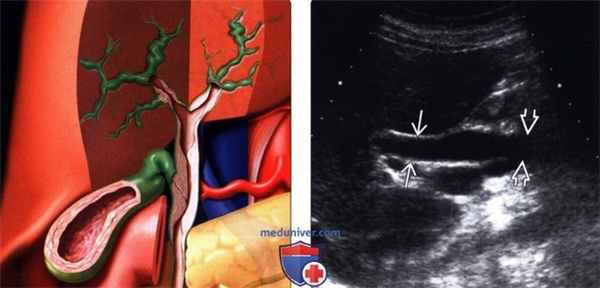

(Левый) На рисунке показаны изменения, развивающиеся при СПИД-ассоциированной холан-гиопатии: множественные участки утолщения стенки и стеноза как внутрипеченочных, так и внепеченочных желчных протоков. Также обратите внимание на утолщение стенки желчного пузыря.

(Правый) При ультразвуковом исследовании ворот печени определяется легкое утолщение стенки расширенного общего желчного протока и резкое конусообразное сужение его дистальной части.